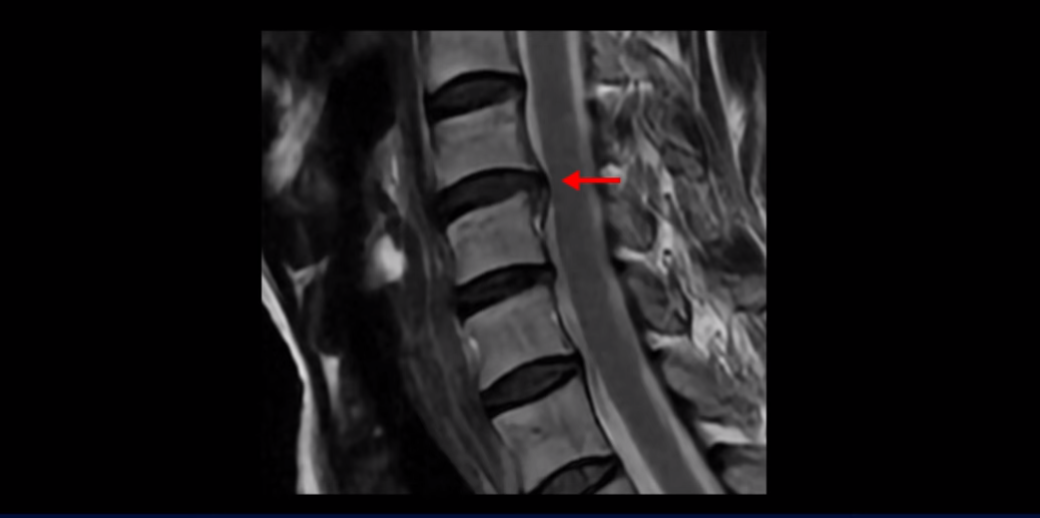

이분 MRI를 보면 세 마디의 퇴행성 목디스크가 있습니다. 4번 5번, 5번 6번과 6번 7번이 세 마디인데

디스크 파열은 4번 5번이 제일 심합니다.

중앙 오른쪽으로 수핵이 밀려 나와있고 밑으로 흘러 내려가 있습니다.

그런데 이 환자분의 방사통은 왼쪽 어깨와 팔입니다. 그래서 이 4번 5번 디스크 파열은 왼쪽 방사통의 원인이 아닌 걸로 보입니다. 6번 7번을 보면 디스크가 왼쪽으로 밀려 나와 있고, 뼈도 자라나 있습니다.

이렇게 뼈가 자라나 있으니까, 신경가지가 빠져나가는 추간공을 보면 여러 마디가 다 좁아져 있습니다.

이런 걸 협착이라고 합니다. 목이 협착이 진행된 것이죠. 그런데 왜 목디스크, 목 협착 치료가 허리보다 훨씬 더 쉽고 빠르다고 하는 걸까요? 그 이유는 목은 하중을 허리보다 훨씬 더 적게 받기 때문입니다. 하중을 적게 받으니까 신경 눌림이 조금만 줄어도 증상이 훨씬 더 빠르게 좋아지는 것입니다.